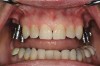

Figure 5  Locator abutments placed on implants can also be used for an implant-assisted prosthesis.

Figure 5